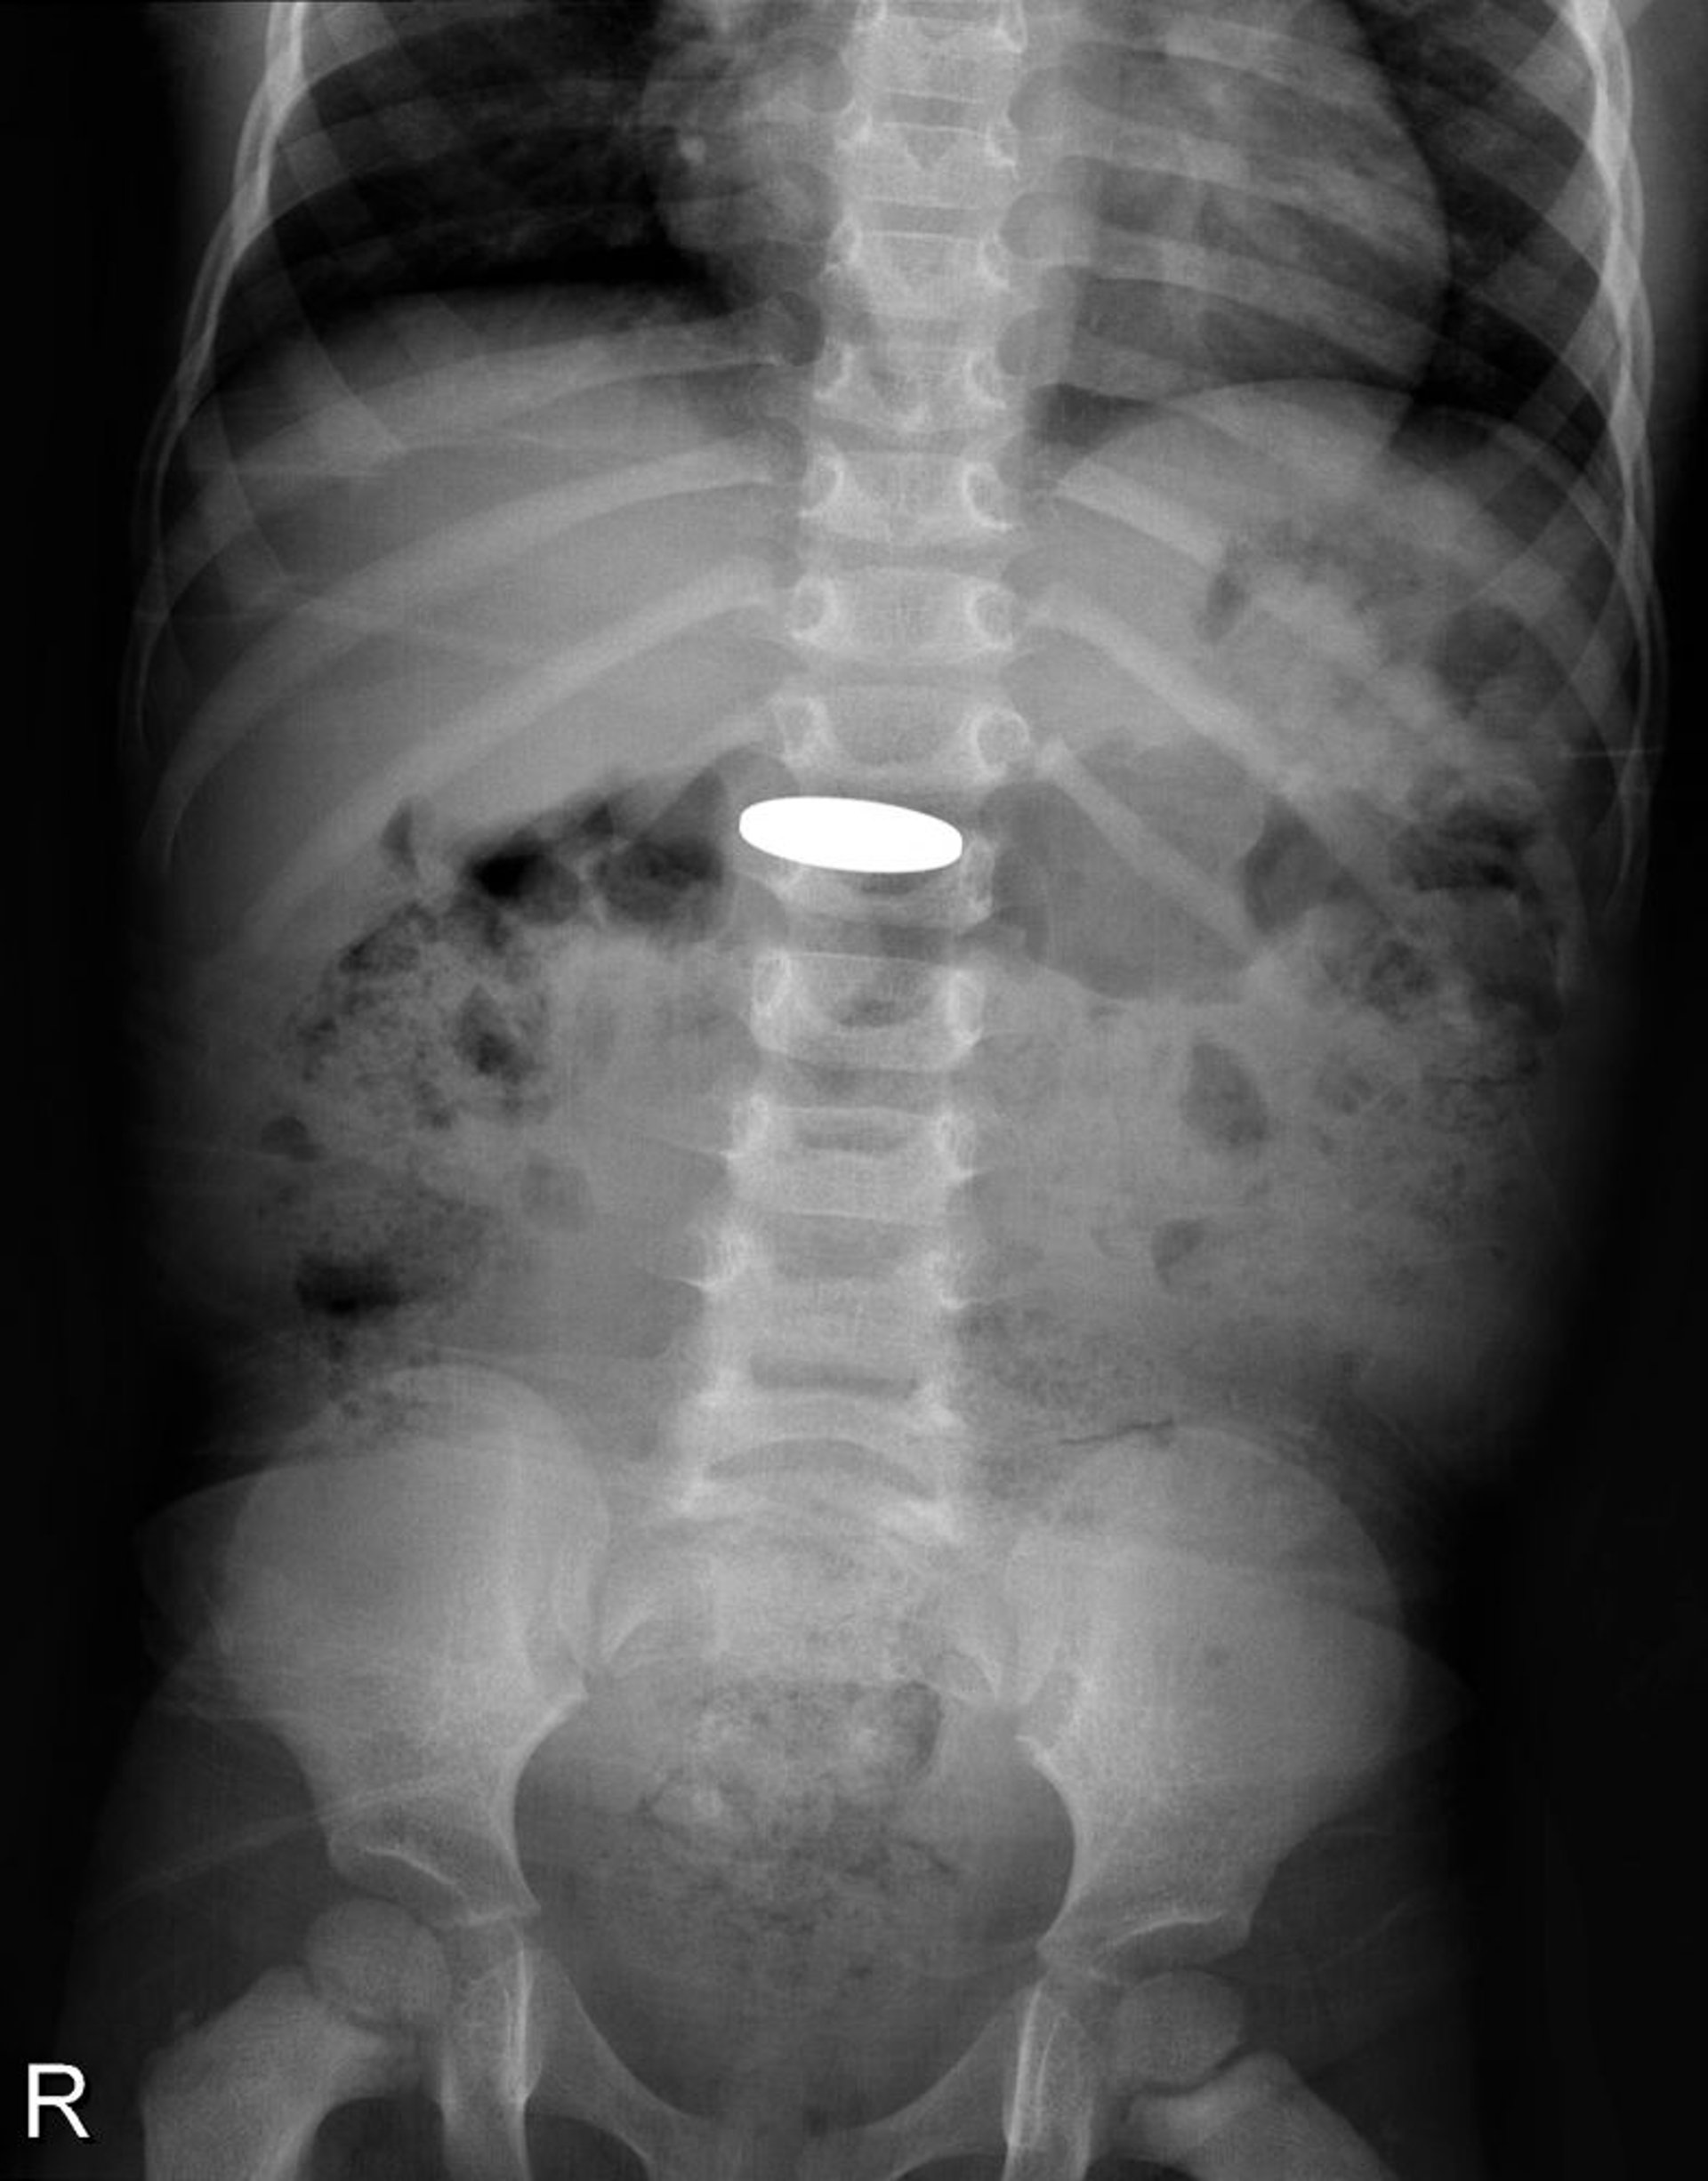

Corps étranger dans le tube digestif (radiographie)

Cette radiographie montre une pièce de monnaie qui a été avalée par un jeune enfant.